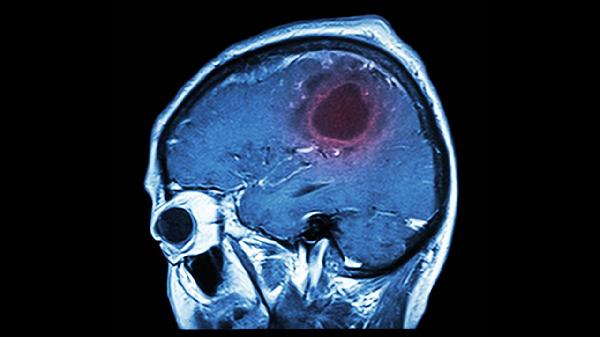

1、脑血栓形成

脑血栓片可用于动脉粥样硬化导致的脑血管局部血栓形成。这类患者通常伴有高血压、高脂血症等基础疾病,表现为突发偏瘫、面瘫或失语。临床常联用阿司匹林肠溶片、阿托伐他汀钙片等药物。服药期间需监测凝血功能,避免与抗凝药物过量联用。